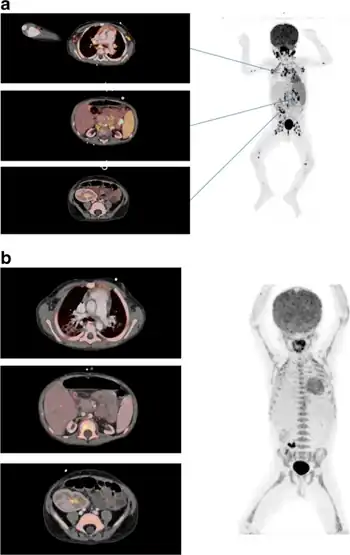

Definitive diagnosis is achieved by biopsying the involved tissue, which will reveal lymphoproliferative neoplasia. Most lesions will show malignant B cells, whereas a minority will show T cell neoplasia. CT imaging may show enlarged lymph nodes or a focal mass. PET scan may be helpful in the evaluation, which may show an increase in metabolic activity (PET avid) lesion, potentially guiding decisions on where to direct biopsies.